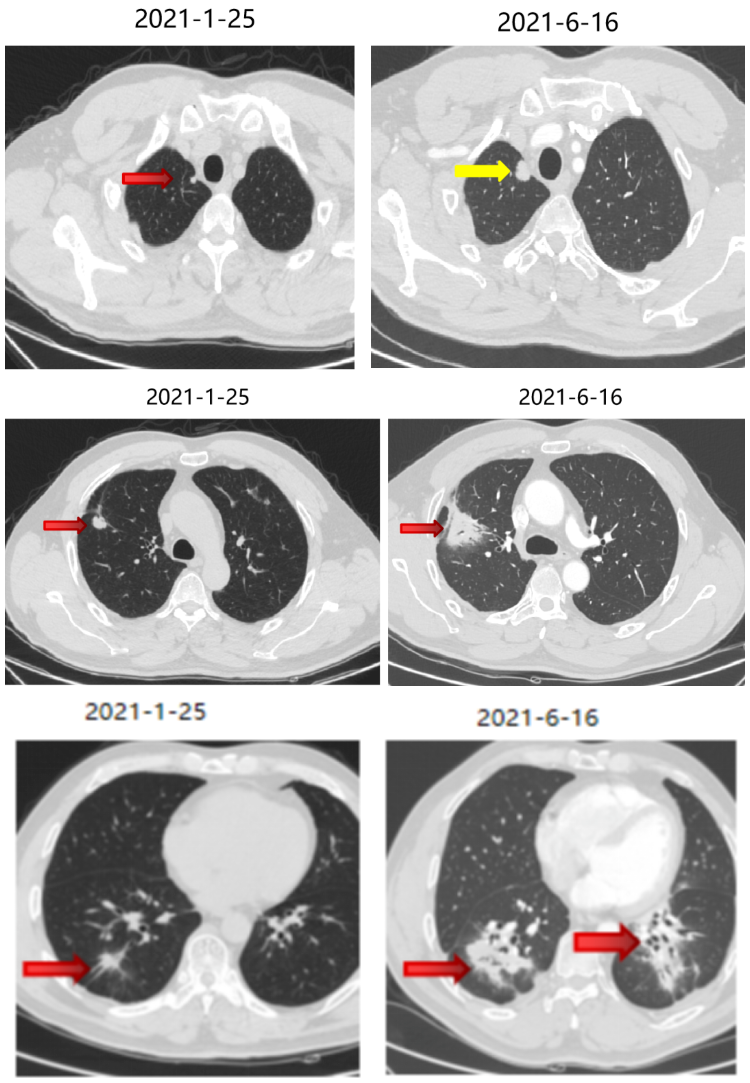

局部治疗(三):粒子植入

2021-10-29、2021-11-1 行CT引导下双肺转移灶放射性碘125粒子植入术。

五线治疗

继续曲氟尿苷替匹嘧啶片(TAS-102)40mg bid+瑞戈非尼40mg qd(2021-11始)至今。

五线治疗疗效:病灶控制良好。

局部治疗(四):粒子植入

2022-4-13、2022-4-15 行CT引导下双肺转移灶放射性碘125粒子植入术。